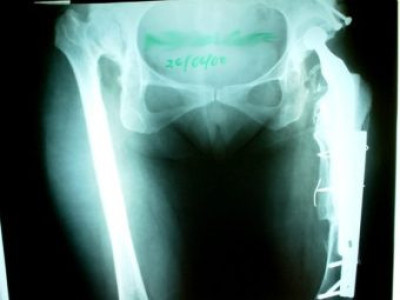

Revisión de prótesis con injerto óseo masivo

Envíado por Dr. Ricardo Antonio Gómez G.